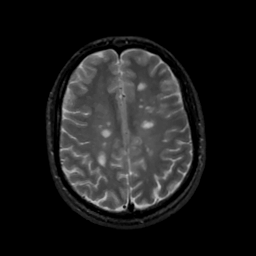

MR Study #13, May 19, 1991 -- Slice #35

[Home][Help][Clinical][Tour 1][Tour 2] Slice 35